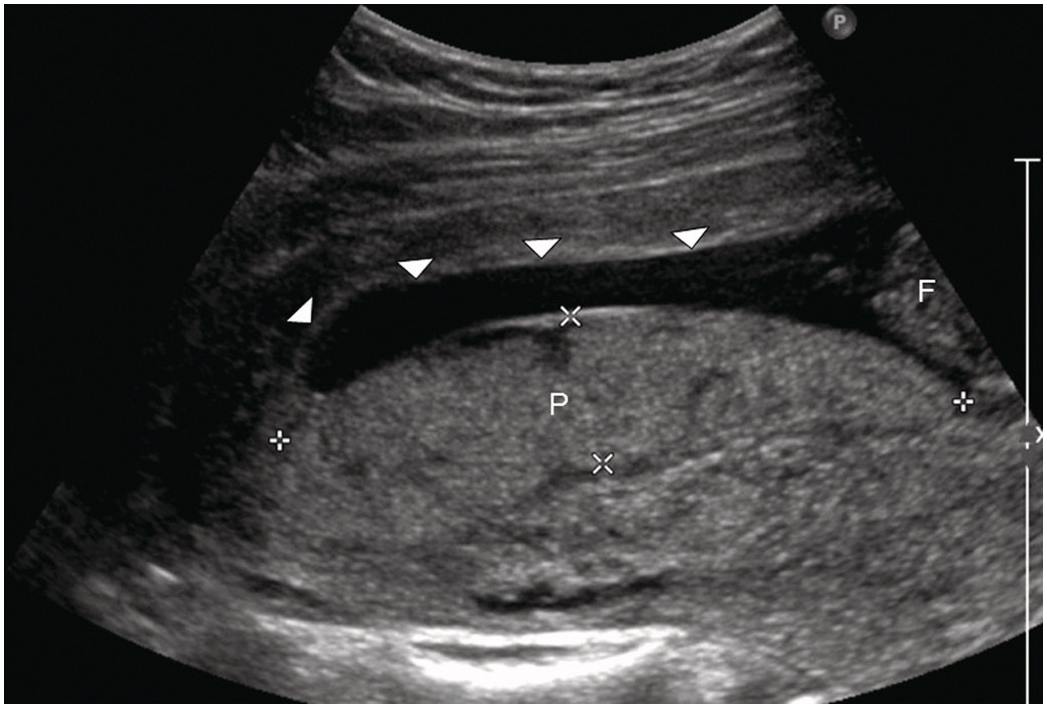

Placenta Model - Taj Scientific Online Store。PVC ZX-1703 Full Term Fetus with Viscera and Placenta at。Mid-trimester sonographic placenta previa thickness and。ペンダーリン シングルカスク ピーテッド。Normal appearance of the anterior placenta: homogeneous。Fetal Growth Restriction: Placental Basis and Implications。。ZX-1700PN Human Placenta Model with Cord at ₹ 5500/piece。Keepsake Items – Midwest Placenta Encapsulation。Placenta Encapsulation - Woven Birth Services。Fetus Baby with placenta 3D Model $25 - .max .unknown .obj。Placenta Encapsulation Training | Lancaster Placenta。Anterior Placenta Labor | TikTok。placentaink on paper201638×40S:54cm×67cm水子の主体に転移して書いた絵です。Anterior/Posterior Placenta? | BabyCenter。